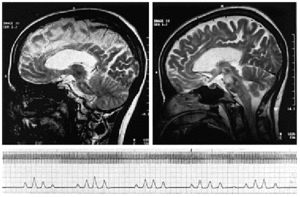

Mujer de 32 años, diagnosticada a los 18 de esclerosis múltiple, que ha cursado de manera recurrente-remitente. En un brote aparecido en febrero de 2001 presentaba, en la resonancia magnética nuclear (RMN), una pequeña lesión nodular hiperintensa localizada en la protuberancia (fig. 1 izda.). En abril de 2002 presenta un brote manifestado por trastorno de la marcha y diplopía horizontal, que evolucionó desfavorablemente hasta presentar hemiparesia izquierda, disartria, incontinencia, crisis tonicoclónicas generalizadas y finalmente coma, por lo que la paciente precisó de ingreso en la UCI. Se realizó una RMN que reveló múltiples áreas de lesión neuronal en protuberancia y mesencéfalo (fig. 1 dcha.). La paciente fue tratada con inmunoglobulinas y plasmaféresis permaneciendo durante todo el ingreso en coma, con GCS 10T y con respiración de Cheyne-Strokes con pausas de apnea de 4-6 s (fig. 1 abajo).